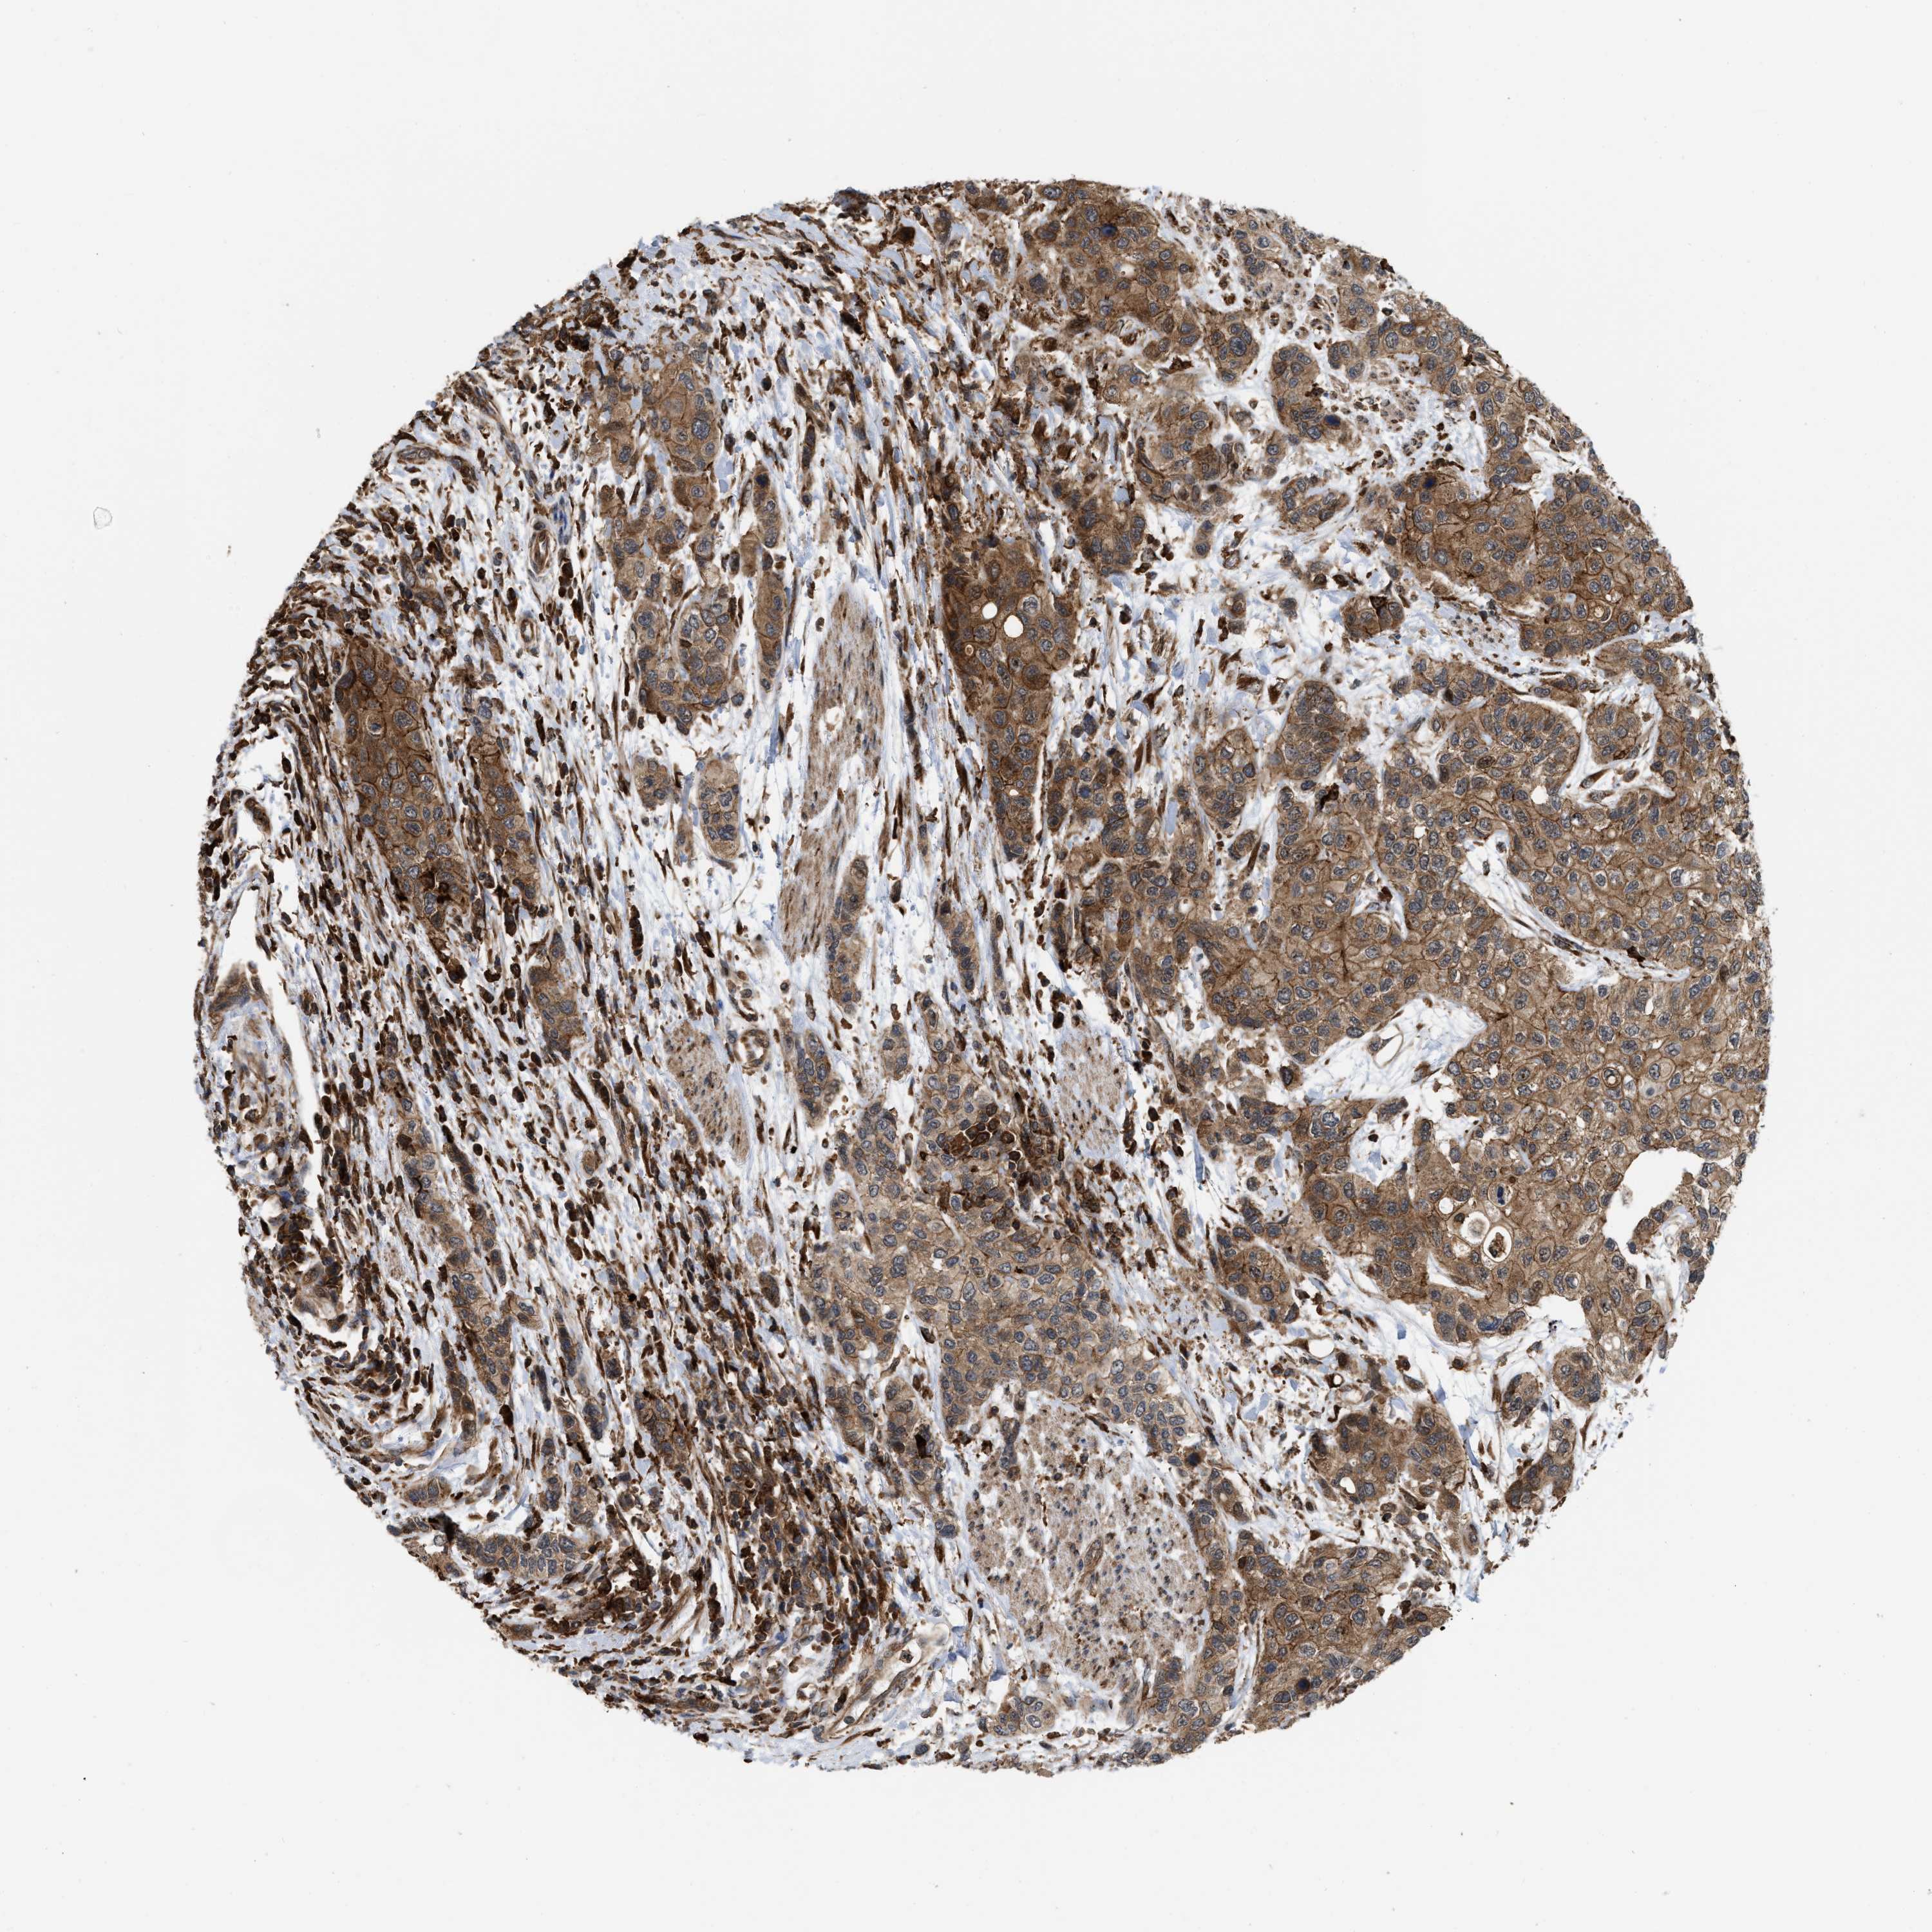

UROTHELIAL CANCER - Protein expressioni

A mouse-over function shows sample information and annotation data. Click on an image to view it in a full screen mode. Samples can be filtered based on level of antibody staining by selecting one or several of the following categories: high, medium, low and not detected. The assay and annotation is described here.

Note that samples used for immunohistochemistry by the Human Protein Atlas do not correspond to samples in the TCGA dataset.

Antibody stainingi

Antibody staining in the annotated cell types in the current human tissue is reported as not detected, low, medium, or high, based on conventional immunohistochemistry profiling in selected tissues. This score is based on the combination of the staining intensity and fraction of stained cells.

Each image is clickable and will lead to virtual microscopy that enables deeper exploration of all samples and also displays staining intensity scores, fraction scores and subcellular localization as well as patient and tissue information for each sample.

Antibody HPA019515

Staining

High

Medium

Low

Not detected

Intensity

Strong

Moderate

Weak

Negative

Quantity

>75%

75%-25%

<25%

None

Location

Urothelial carcinoma, Low grade

Urothelial carcinoma, High grade